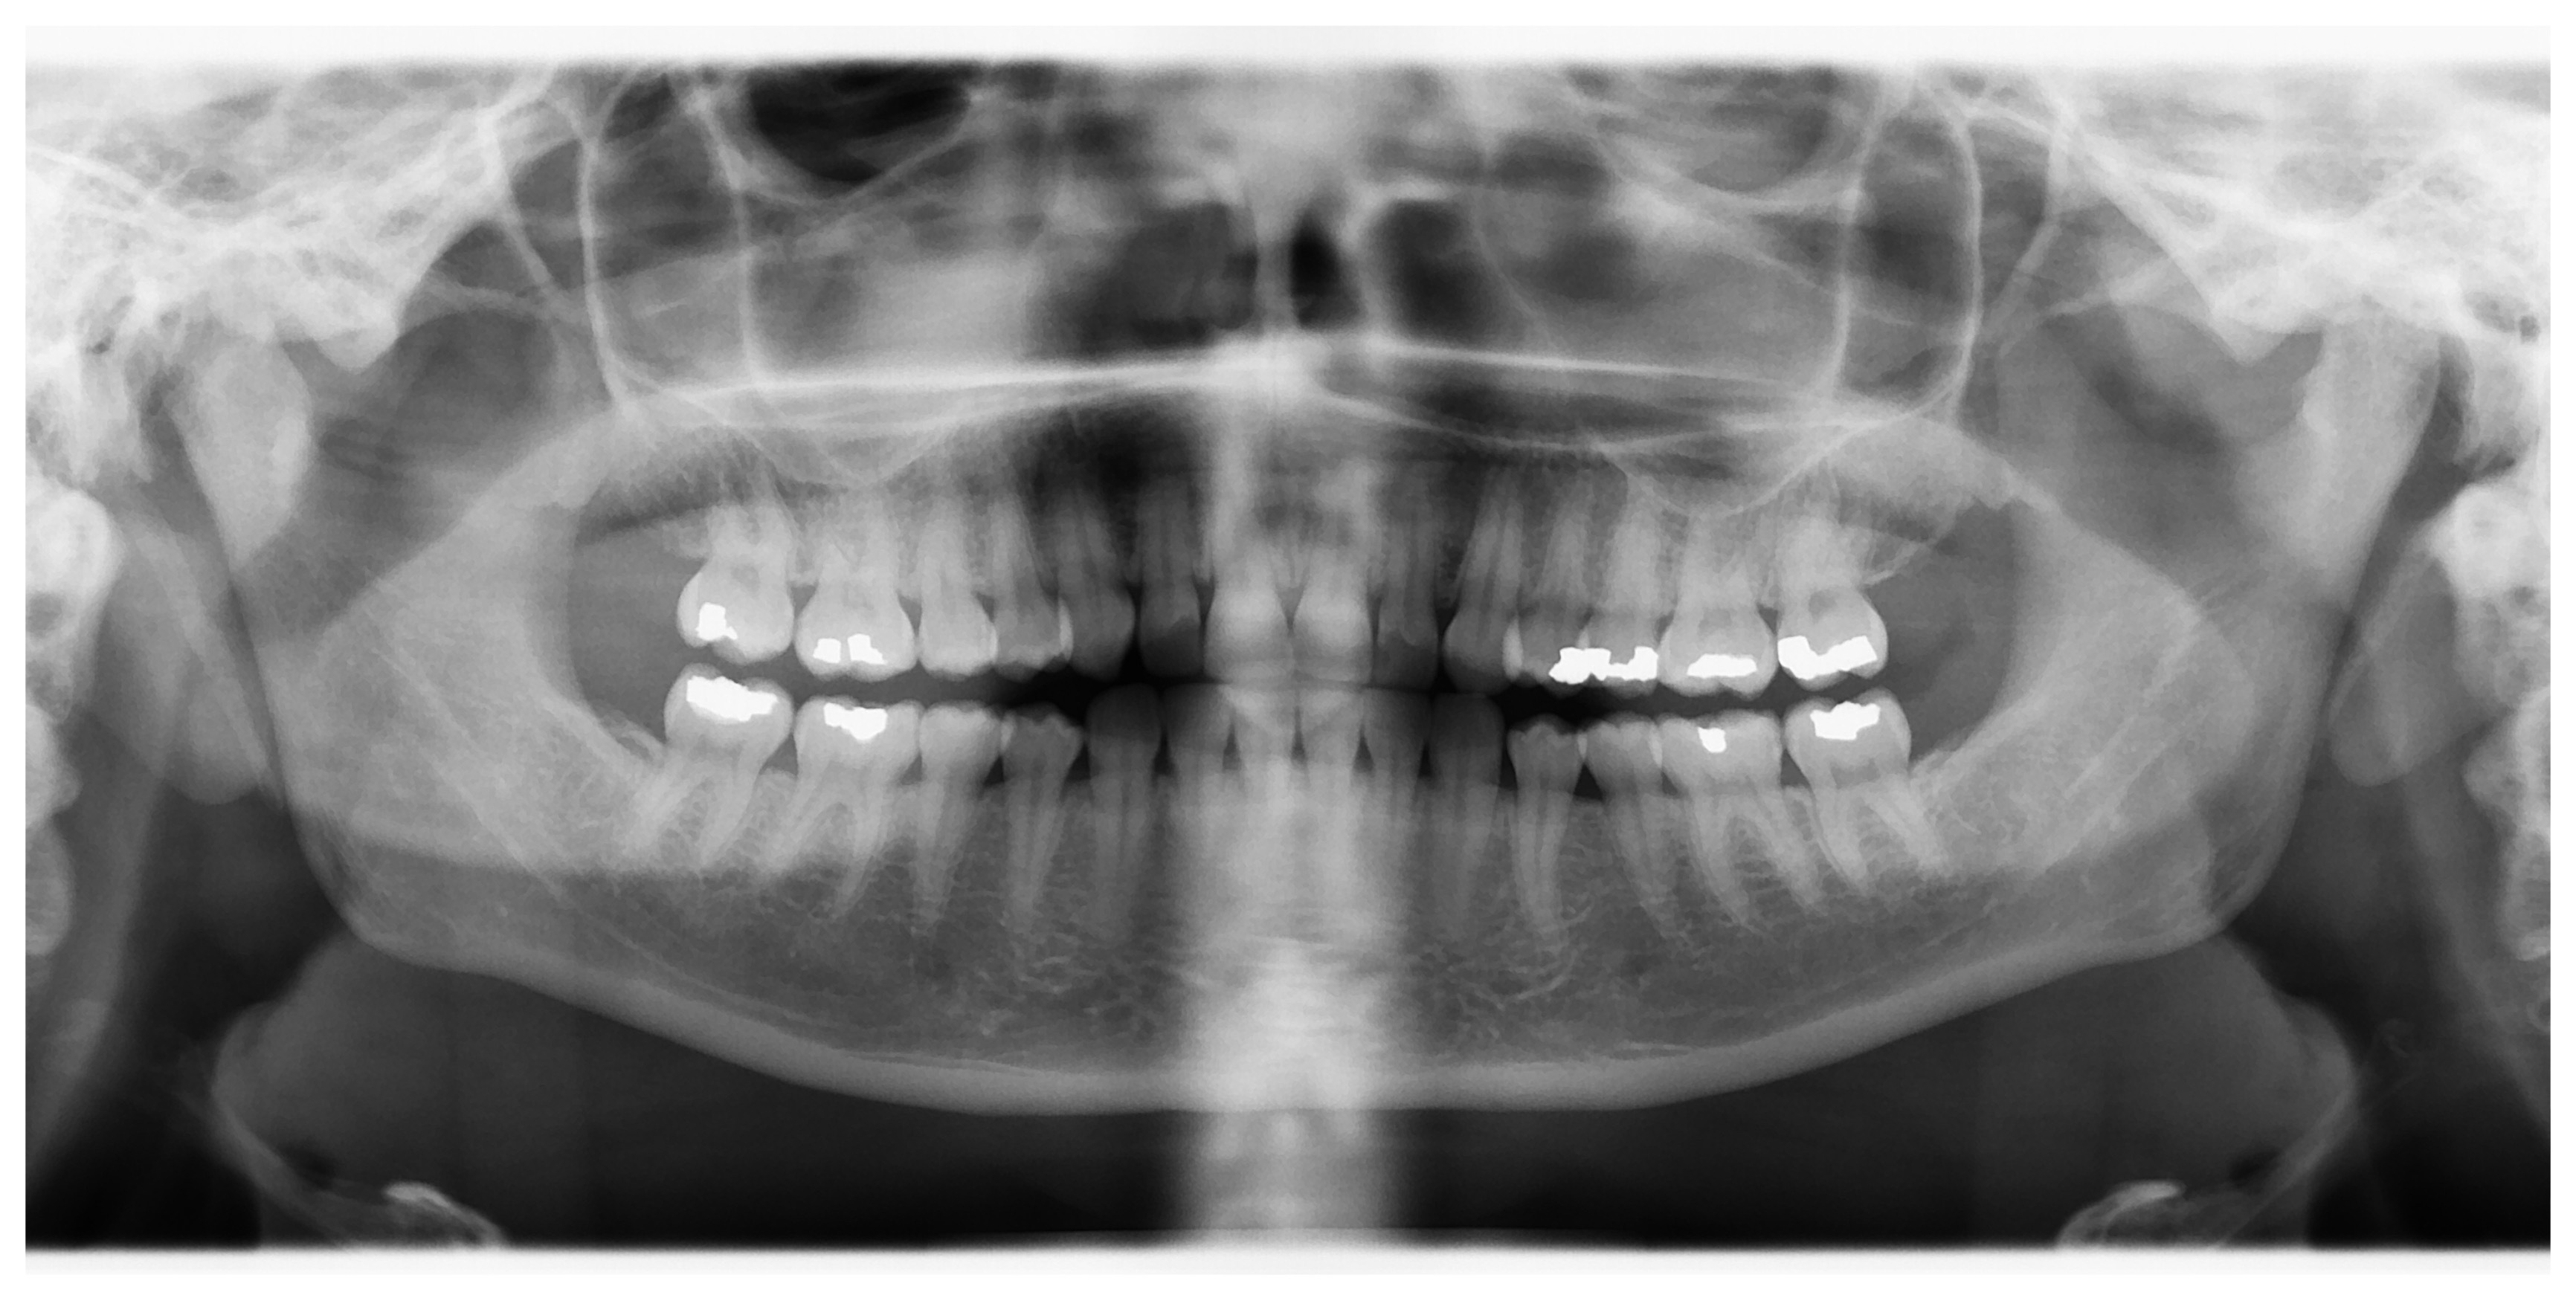

Panoramic X-ray during initial consultation – multiple caries under unexact fillings, periapical inflammation, inadequate root canal treatments

Panoramic X-ray made three years after termination of treatment – new root canal treatments, new precise crowns and bridges, patient without any pain or other problems